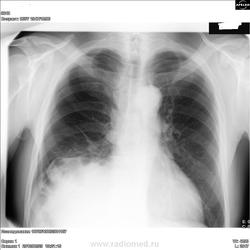

ХИЛАИДИТИ СИНДРОМ – интерпозиция печеночного угла толстой кишки между печенью и диафрагмой. Бывает постоянная (фиксация спайками) и перемежающаяся. Основные клинические проявления: чувство тяжести и боли в правом подреберье, запоры, частичная и даже полная кишечная непроходимость, уменьшение высоты печеночной тупости (если кишка содержит газ). Печеночная тупость может уменьшаться (или отсутствовать) также при эмфиземе легких, атрофическом циррозе печени и перфорации желудочно-кишечного тракта.

Хилаидити.

Как-то контур диафрагмы и ее высокое стояние не нравится - возможно поддиафрагмальный абсцесс

Хотя нет, не абсцесс))

А интепозиция толстой кишки подойдёт?

Это одно и то же. Ещё уважаемый коллега Nikolas, не указал, что интерпозиция толстой кишки может и никак не проявляться.